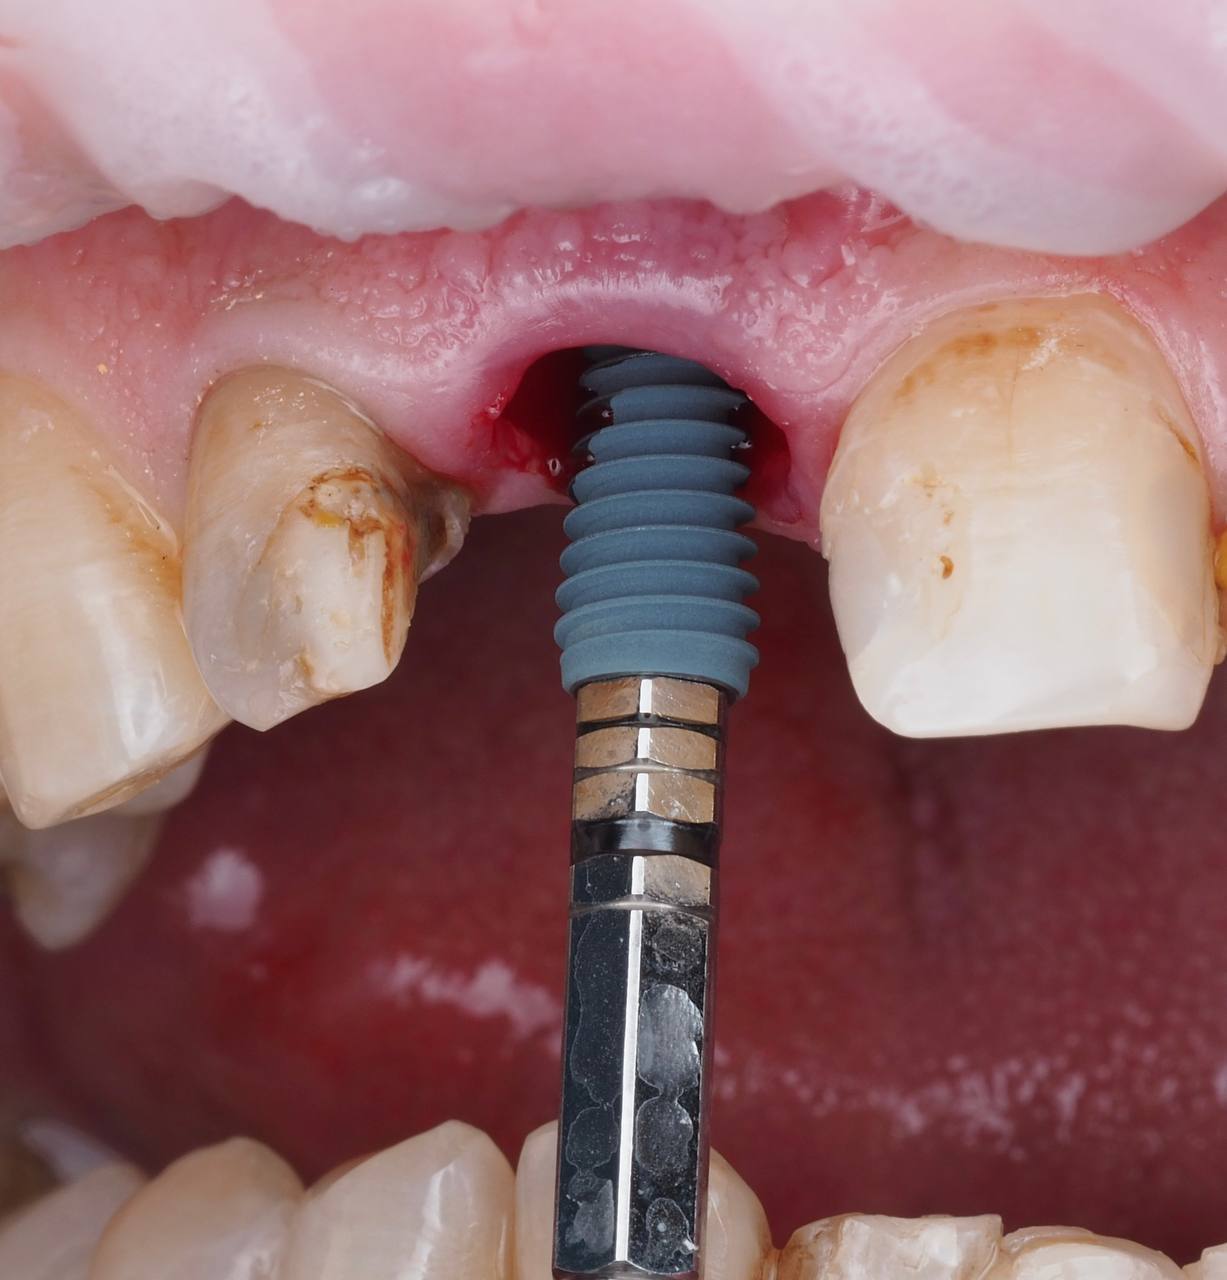

Одномоментная имплантация 1.1

AnyRidge, мультиюнит Octa, CCT, временная коронка